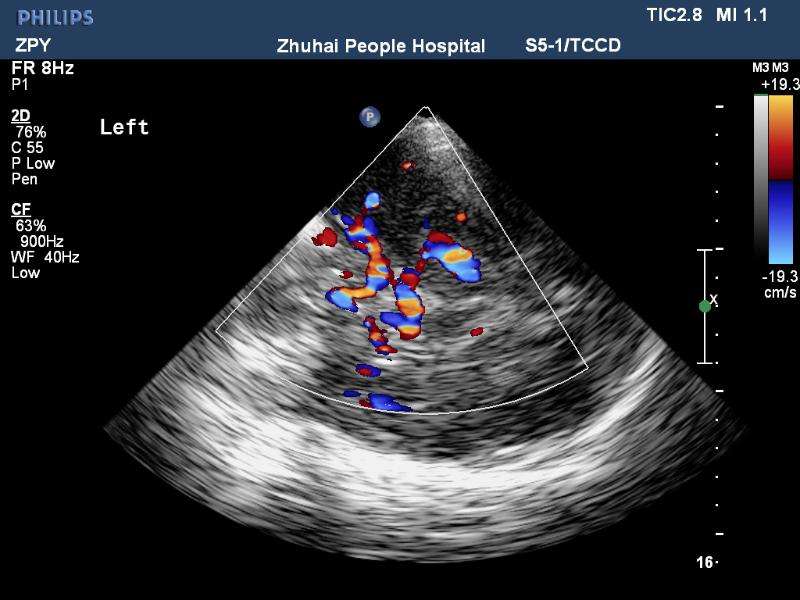

經顱彩色編碼雙功能超聲(transcranial color-coded duplex sonography

TCCD)是一種非侵入性發現顱內動脈異常血流動力學狀態的可靠方式。TCCD成像原理是在TCD基礎上增加了二維灰階實時顯像以及彩色編碼雙功能超聲成像,在二維顯示顱內解剖結構的同時,同時對運動紅細胞產生的多普勒頻移進行彩色編碼。應用TCCD檢測時可以通過在感興趣區內多點取樣,得出取樣容積內多普勒頻移曲線,通過雙側對比、左右對比以及前后對比,綜合評價缺血性腦血管病受檢者Willis環的血流動力學變化。

依據多普勒頻移值編碼成像即f-TCCD:依賴運動紅細胞所產生的多普勒頻移值進行計算機編碼,可以顯示血流方向和測算血流速度,需要校正多普勒取樣角度,角度及篩查深度依賴性較大,較易產生運動偽像。(2)依據運動紅細胞所產生的總能量進行編碼成像即p-TCCD:只與運動紅細胞所產生的總能量有關,無需校正多普勒取樣角度,對于受取樣角度影響較大血管病變,諸如大腦后動脈(PCA),大腦中動脈(MCA)M2段,大腦前動脈(ACA)A1段有一定的幫助作用,信噪比更高,不易產生混疊效應。p-TCCD相對f-TCCD而言,缺點是不能顯示血流方向,對顯示狹窄處高速血流敏感性較低。